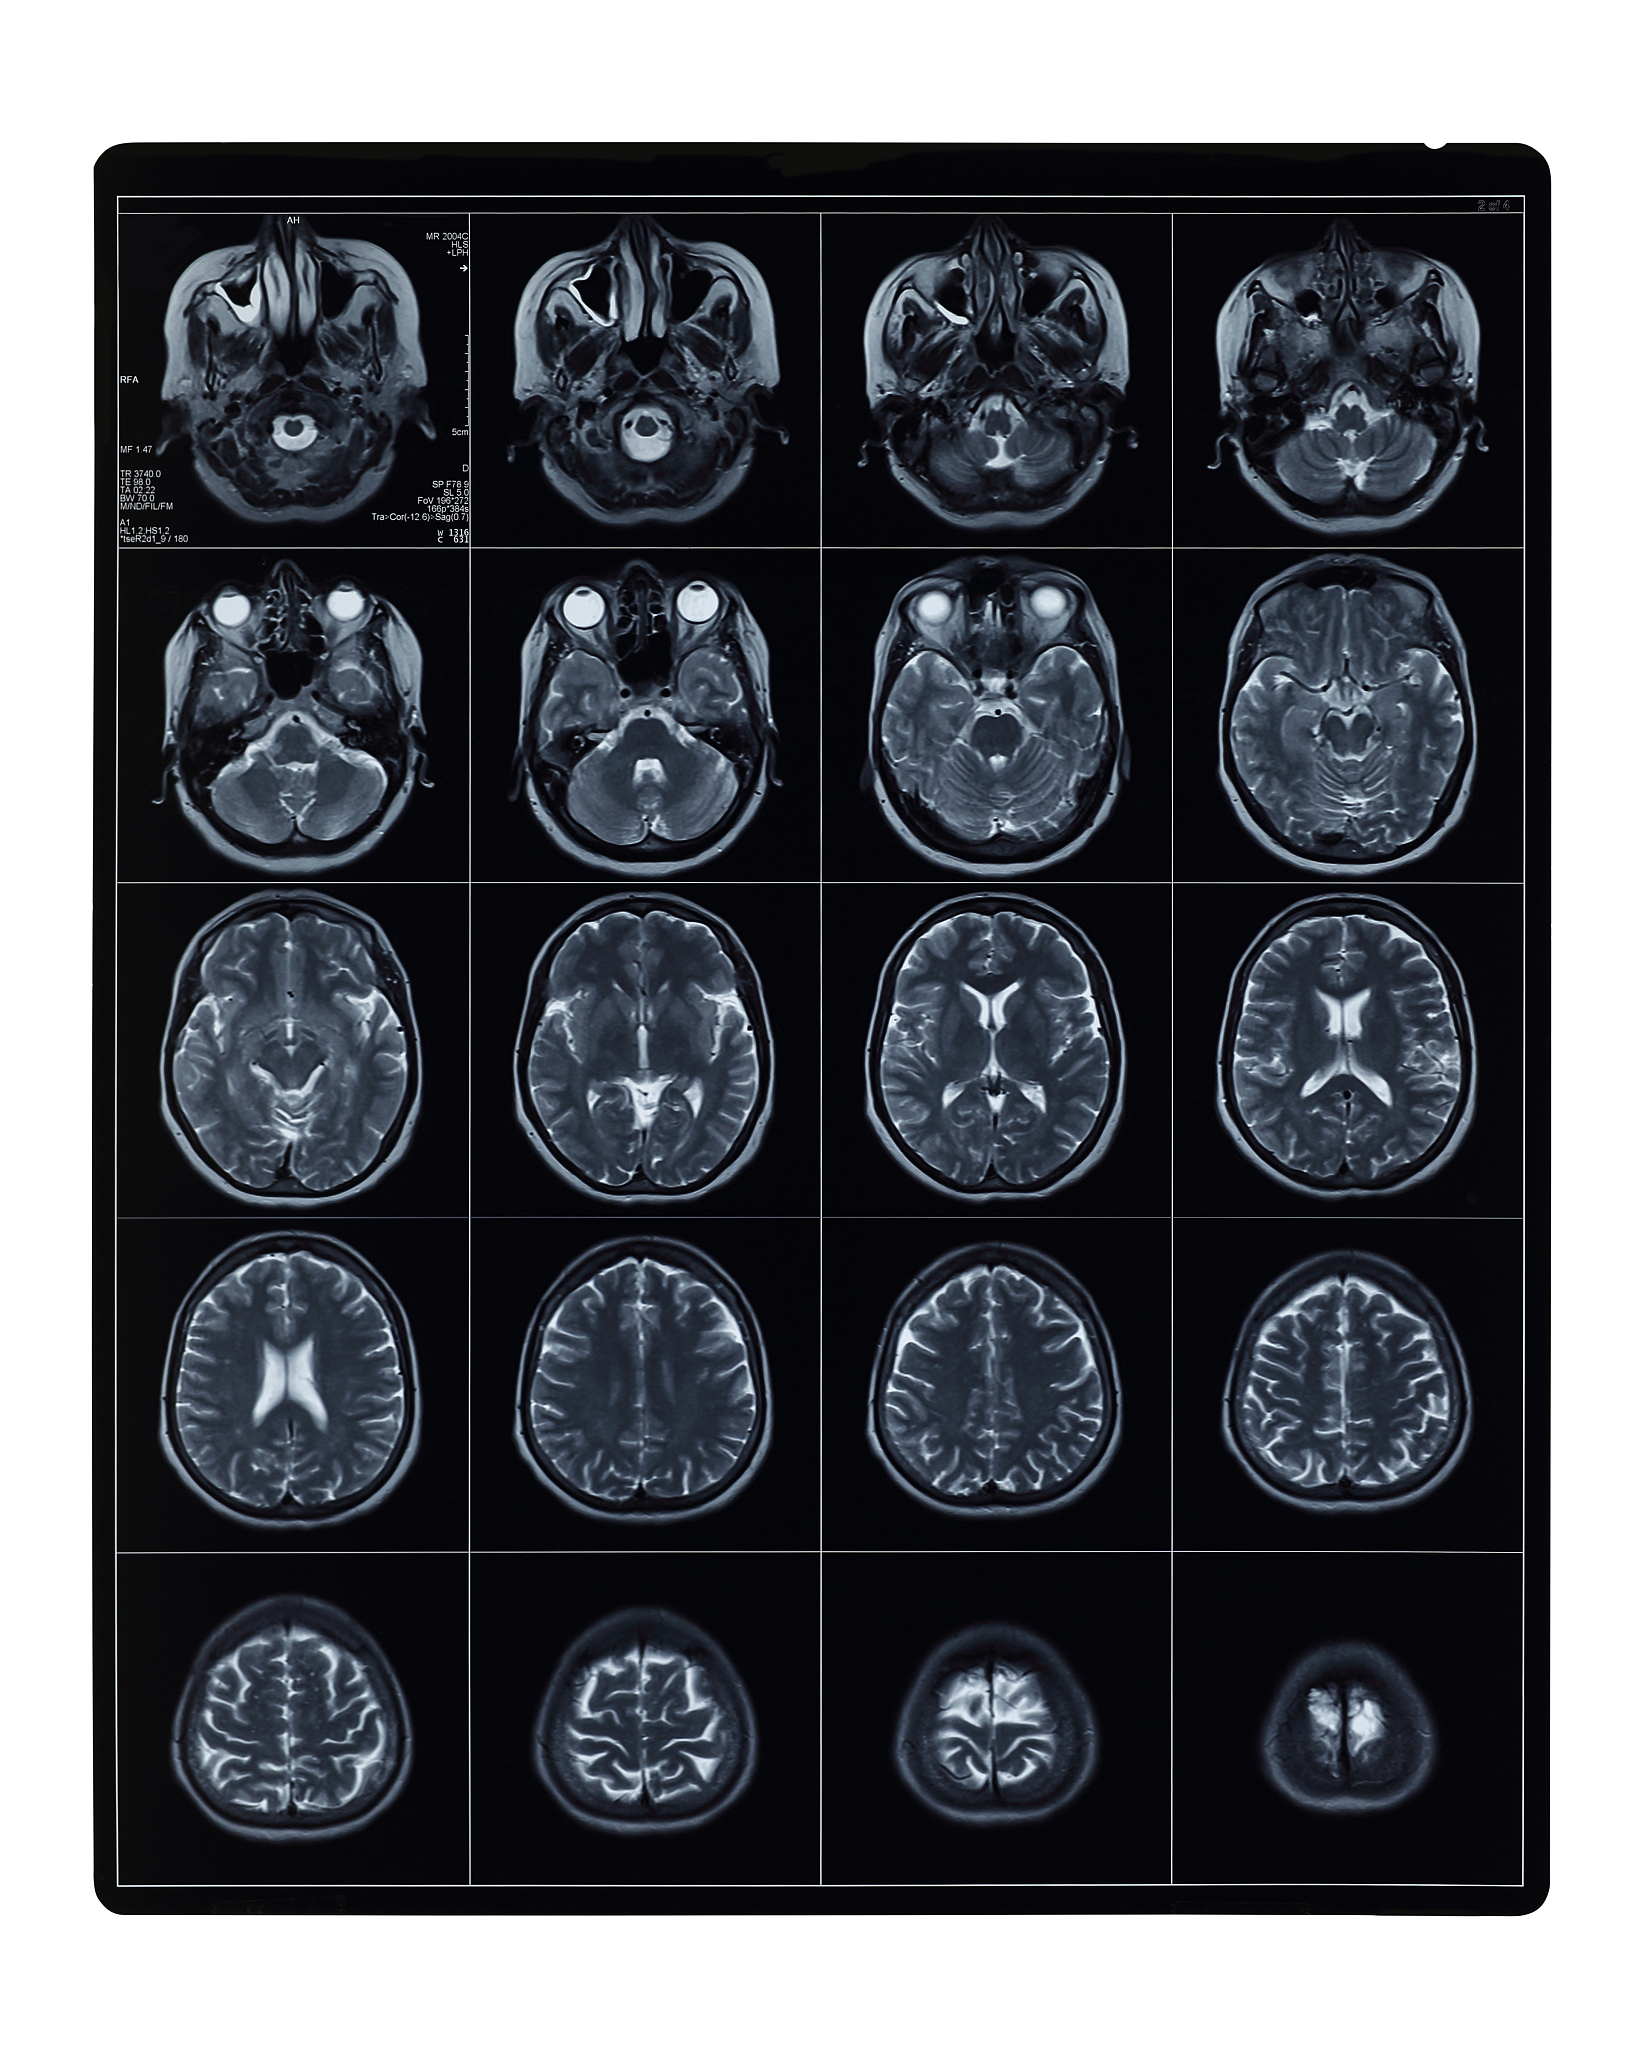

磁共振FLAIR图像:为何脑脊液信号会变低?

磁共振FLAIR(Fluid-attenuated inversion recovery,液体衰减反转恢复)成像技术,能够清晰区分脑组织与脑脊液(CSF)。这一技术的关键在于利用CSF的信号特性,抑制脑组织信号,从而突出显示病变区域。那么,FLAIR图像中CSF为何呈现低信号呢?

FLAIR成像的核心机制在于'反转脉冲'。在激发脑组织信号之前,先施加一个180度的反转脉冲,此举能有效抑制CSF信号,而保留脑组织信号。因此,在最终呈现的FLAIR图像上,脑组织区域信号高亮,而CSF区域则呈现低信号,形成鲜明对比。

• 高自由度,低信号: CSF作为一种液体,分子自由度高,相互作用力弱,导致其自旋运动速度快,T1和T2弛豫时间短,最终导致信号强度低。

总而言之,磁共振FLAIR成像中CSF呈现低信号并非偶然,而是由CSF本身的物理性质和成分共同决定的。这一特性使得FLAIR成像成为一种强大的神经影像学工具,能够帮助医生更好地诊断和评估脑部疾病。